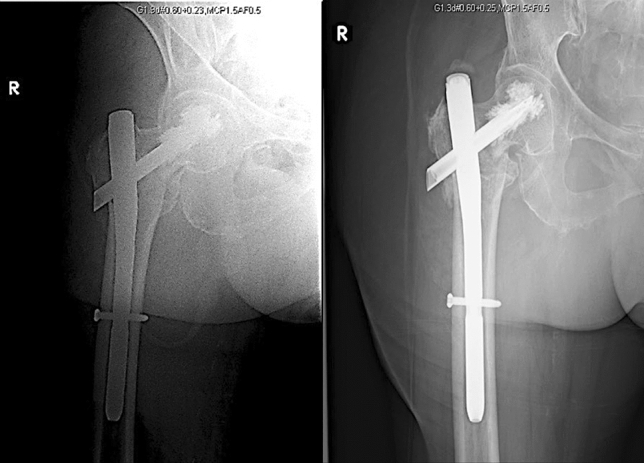

Fig. 2.

69/M who sustained an AO/OTA 31-A3 fracture which was fixed with a long TFNA and cement augmentation. First and second from left: immediate post-op; third and fourth: 6 months post-op showing a united fracture and failure of both distal screws

Two patients in our pool had implant failure, specifically breakage of the distal locking screws (Fig. 2). However, documentation reveals that the screws failed after their fractures had already healed, sometime between 3- and 6-months post-surgery. Both patients had cement augmentation, had been weight-bearing as tolerated on their surgically fixed limbs, and there was no note of any significant trauma prior to screw failure. They were also asymptomatic. Other than being an incidental finding, one possible explanation for this is that the points of the screw failure were the either the weakest in the entire implant-bone interface, or the area with the greatest stress concentration—an area that is traditionally associated with the femoral head–neck region, which usually leads to either varus collapse and cut-out, or nail breakage at the hole for head element insertion [6, 17–19, 24]. This suggests that the TFN-A with an augmented head–neck region in the setting of a healed proximal femur fracture may have a different pattern of force transmission as well as areas of stress concentration compared to those previously described for proximal femur intramedullary implants.